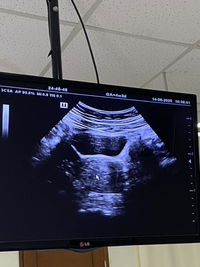

Hai bun.mau tanya kalo mau USG bayar nya berapa ya kira2 sama harga obatnya.

Ke klinik yg ada usg aja bun biasanya lebih murah, di bogor ada yg 180rb usg 2d (dpt print). Kalau di RS aku pernah sampe 450rb ga dapet apa”